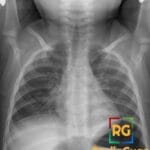

62 yr female presenting with a palpable right lower quadrant mass and chronic abdominal pain.

Diagnosis: Appendiceal Mucocele

- Clinical: Middle-aged to elderly populations; 50% are asymptomatic; symptomatic cases present with a palpable right lower quadrant mass, abdominal pain, or pelvic pain.